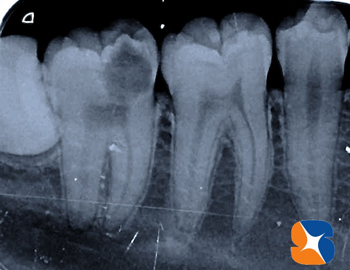

横向きの親知らず レントゲンの結果、右下には大きな虫歯(奥歯)と横向きの親知らずを確認。左下にも、横向きの親知らずを確認出来ました。